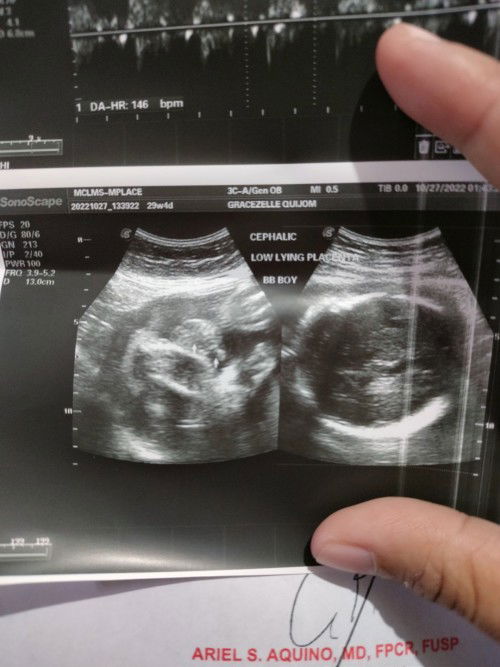

Good evening mga mommy!! 💖 Ask lang po pano nyo po napataas ang placenta nyo? Im currently 29 weeks and 4 days and sabi sa Ultrasound ko Low lying placenta daw po. May chance po ba ma tumaas ulit ang placenta at ma-normal delivery si baby? Thank you in advance po sa mga advice and tips ❤️ #pleasehelp #advicepls #firsttimemom #FTM